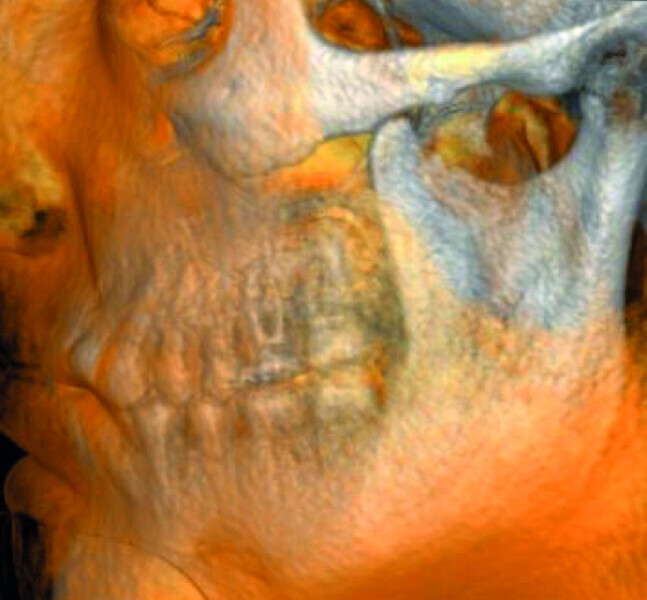

Maxillary sinus and root canal therapy complications